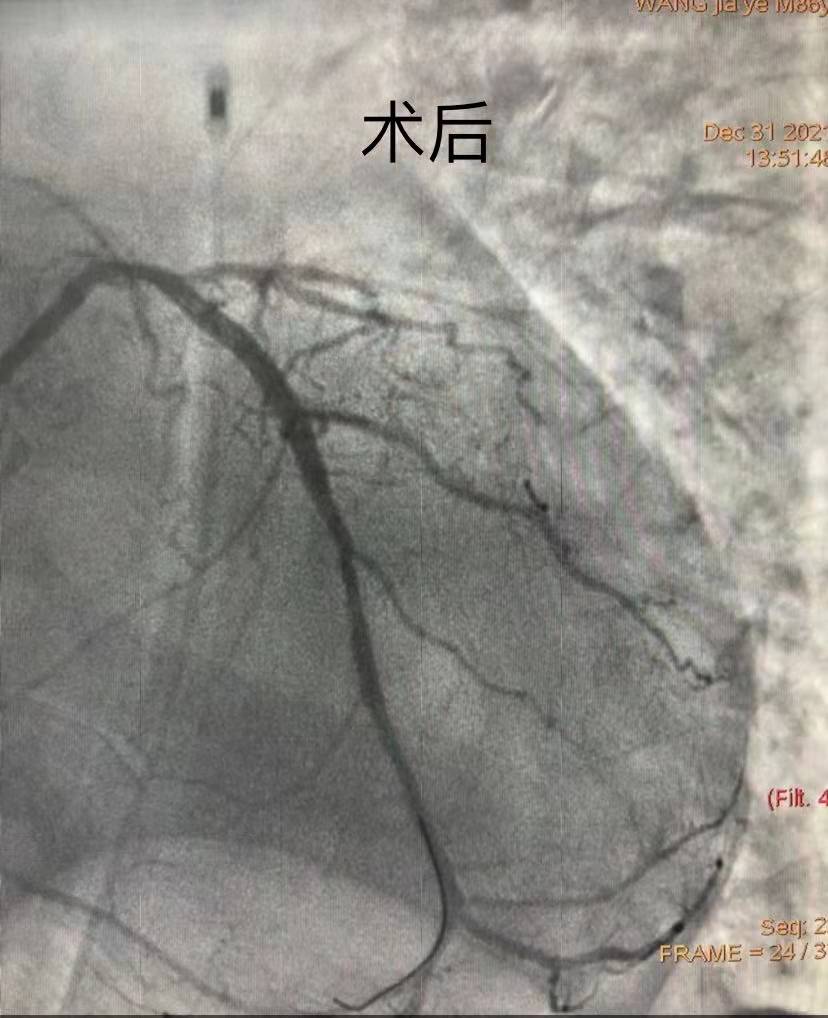

團(tuán)隊(duì)綜合考慮后判斷,LCX是此次心肌梗死的“元兇”。開通病變部位的機(jī)會(huì)只有一次,必須做到“快、準(zhǔn)、狠”。汪院長團(tuán)隊(duì)經(jīng)驗(yàn)豐富,技術(shù)嫻熟,導(dǎo)絲小心通過,球囊充分?jǐn)U張,最后在病變部位植入支架,所有操作一氣呵成。復(fù)查造影顯示,病變部位狹窄小于10%,手術(shù)獲得成功。

術(shù)后72小時(shí)尤為重要,心血管內(nèi)科團(tuán)隊(duì)不敢有絲毫懈怠,護(hù)士長彭鳳艷帶領(lǐng)護(hù)理團(tuán)隊(duì)嚴(yán)格床旁交班,事無巨細(xì)地交代注意事項(xiàng)、皮膚及管道護(hù)理,嚴(yán)密監(jiān)測患者生命體征。三天后,患者生命體征逐漸平穩(wěn)。1月3日經(jīng)綜合評(píng)估后,拔除IABP導(dǎo)管,復(fù)查心臟彩超,各項(xiàng)評(píng)分?jǐn)?shù)值恢復(fù)良好。經(jīng)過10余天的精心治療和護(hù)理,患者于1月12日康復(fù)出院。